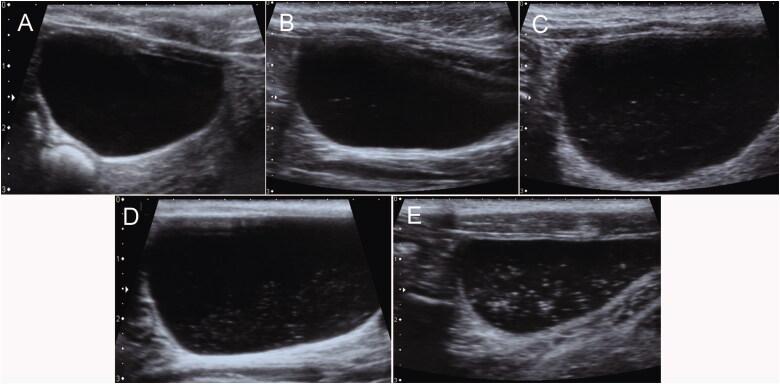

Renal cortical anisotropic backscatter artifact (CABA) is a hyperechoic region of the renal poles where the insonation of sound beams is perpendicular to the renal tubules within the renal cortex.

To determine whether renal CABA can be observed in healthy cats and to compare the echogenicity of renal CABA with that of the spleen and liver.

Images of the spleen, liver, kidneys, and urinary bladder were acquired from 30 clinically healthy cats with renal CABA. Echogenicity differences among organs and echo scores within urine were recorded and analyzed. All ultrasound images were acquired using a 7.2-14-MHz linear transducer. Univariate logistic regression was used to assess the associations between the presence of renal CABA and various variables.

The prevalence of the renal CABA was 86.7% (26/30) and 93.3% (28/30) according to different observers. The reproducibility of renal CABA is substantial to excellent. The renal CABA echogenicity was greater or equal to the spleen and greater than the hepatic echogenicity in 90.0% of cats (27/30). For comparison with the spleen and liver, there were three and six combinations of echogenicity differences using the CABA and non-CABA regions, respectively. The renal cortical echogenicity in the CABA region was higher than the liver in all subjects. Renal CABA was not associated with age, body weight, gender, body condition score, or lipid droplets in the urinary bladder.

Renal CABA was present in most healthy cats and could be used for echogenicity comparisons with the liver and spleen.

肾皮质各向异性反向散射伪像(CABA)是肾脏两极的一个高回声区域,在该处声束的照射与肾皮质内的肾小管垂直。

确定健康猫是否可以观察到肾 CABA,并比较肾 CABA 的回声与脾脏和肝脏的回声。

对 30 只具有肾 CABA 的临床健康猫的脾脏、肝脏、肾脏和膀胱的图像进行采集。记录和分析器官之间的回声差异和尿液内的回声评分。所有超声图像均使用 7.2-14MHz 线性换能器获取。单变量逻辑回归用于评估肾 CABA 的存在与各种变量之间的关联。

根据不同观察者,肾 CABA 的患病率分别为 86.7%(26/30)和 93.3%(28/30)。肾 CABA 的可重复性为中等至极好。在 90.0%(27/30)的猫中,肾 CABA 的回声强度大于或等于脾脏,且大于肝脏回声强度。与脾脏和肝脏相比,分别使用 CABA 和非 CABA 区域有三种和六种回声差异组合。在所有对象中,CABA 区域的肾皮质回声均高于肝脏。肾 CABA 与年龄、体重、性别、身体状况评分或膀胱内的脂质滴无关。

大多数健康猫存在肾 CABA,可用于与肝脏和脾脏进行回声比较。